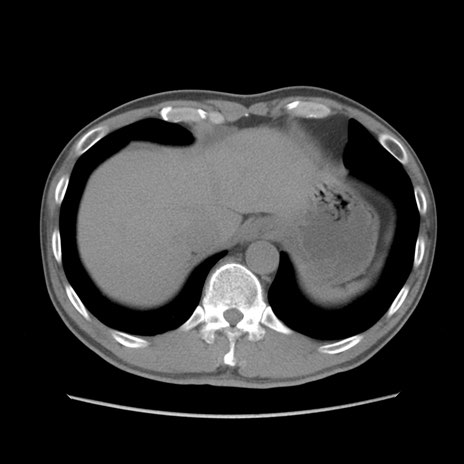

症例56 CT(横断像)